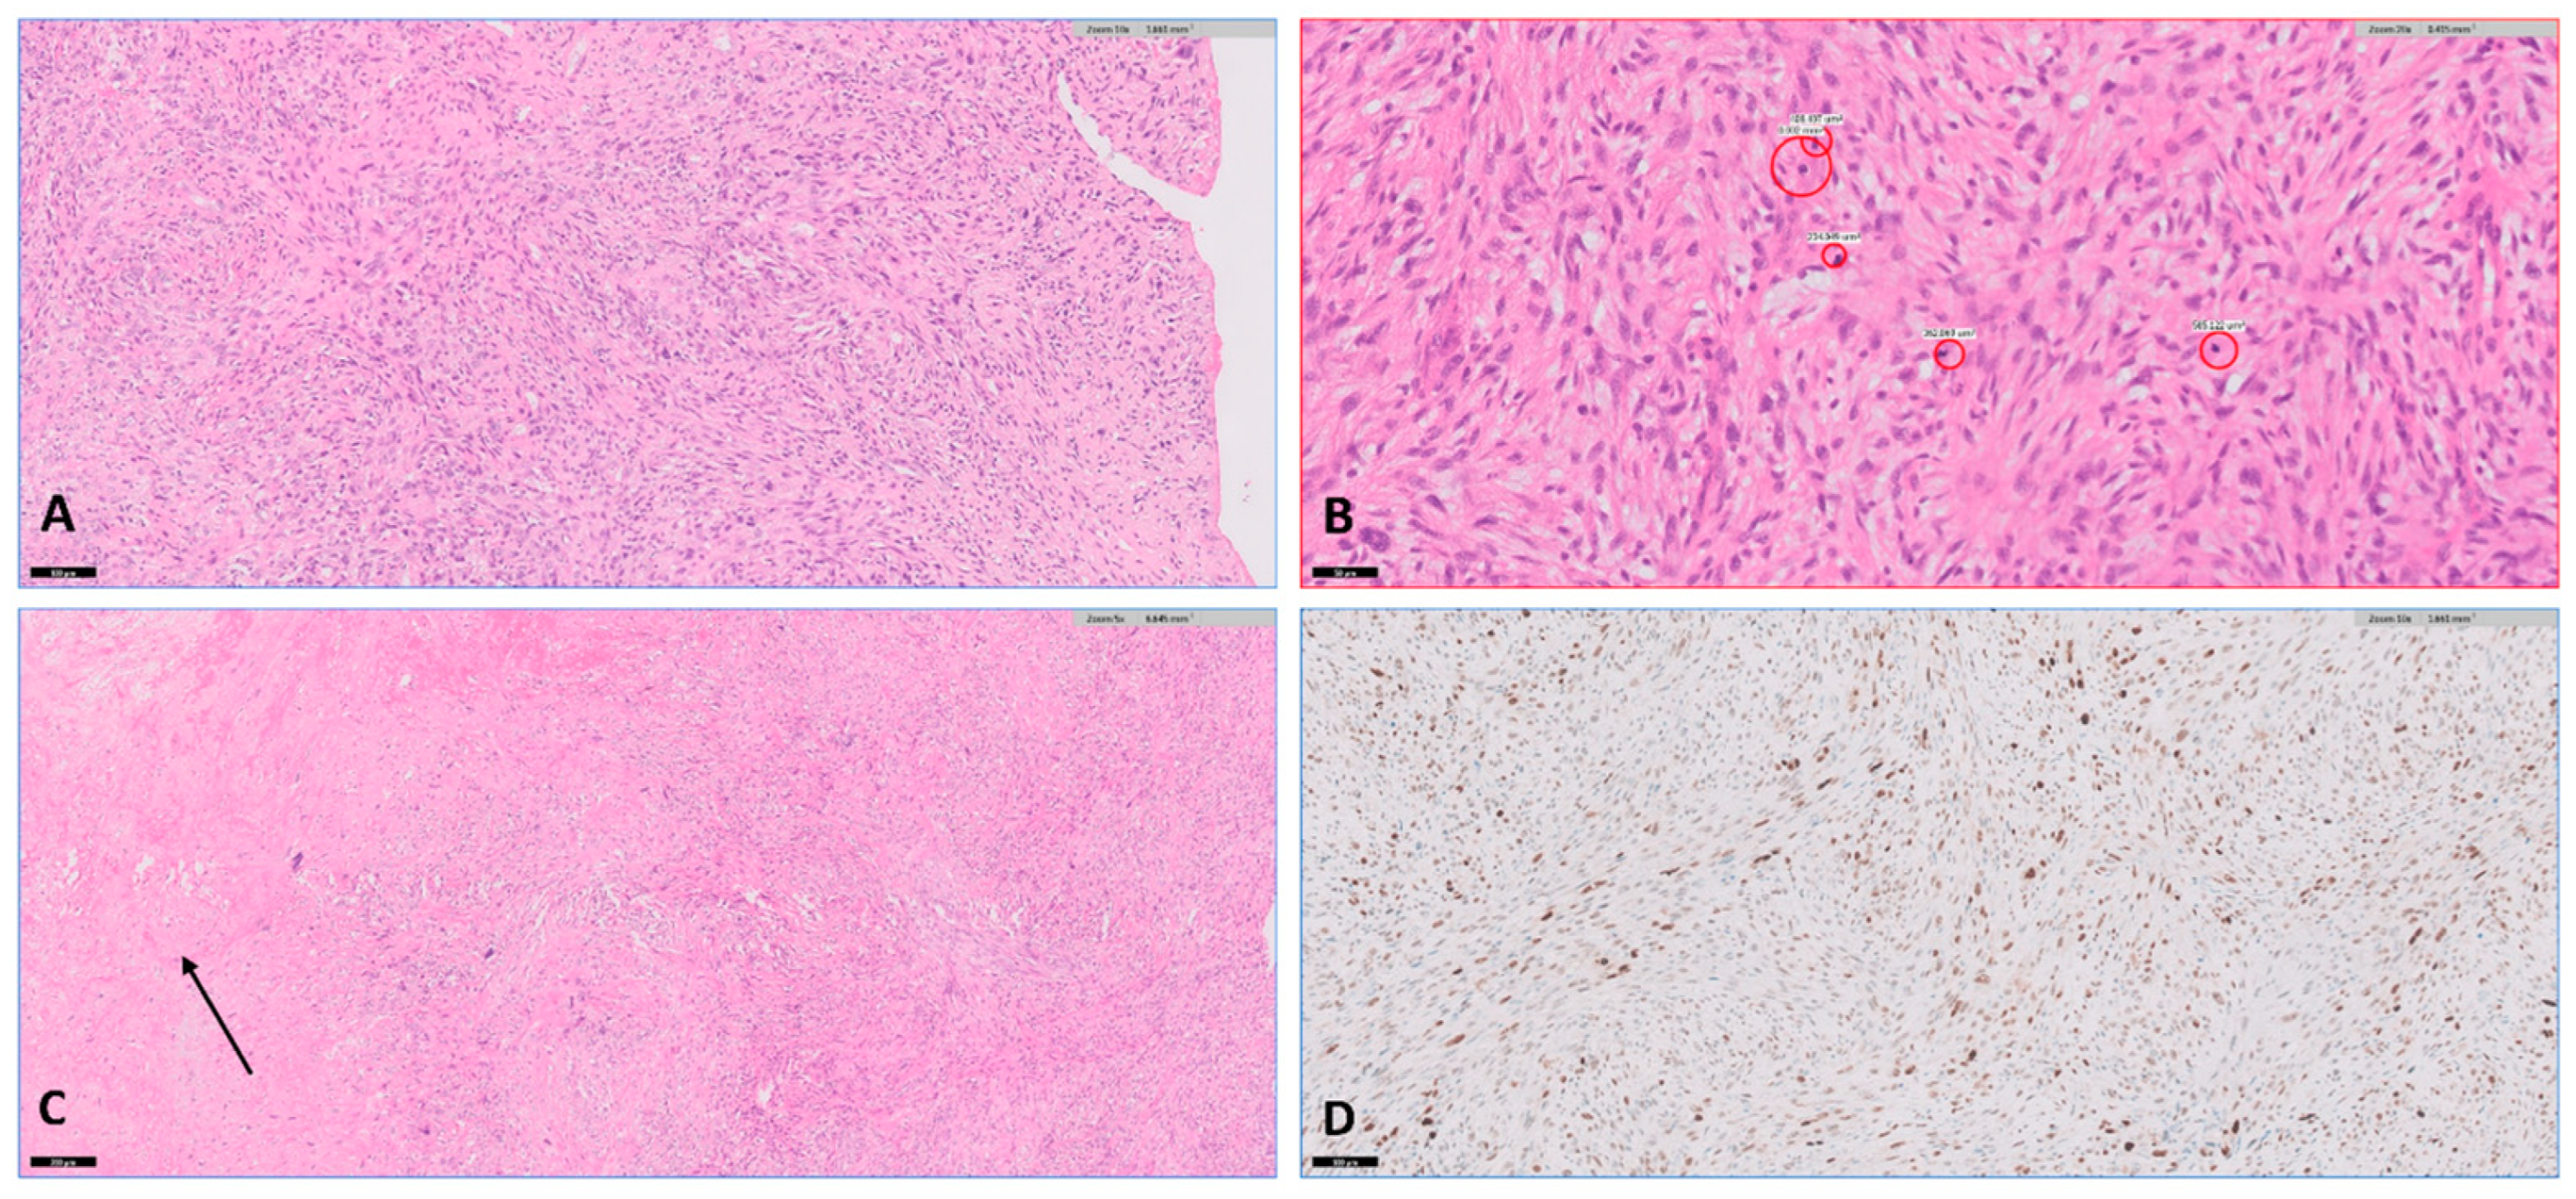

A repeat echocardiogram after a month revealed a very large, multilobar, redundant mass occupying most of the LA cavity, with a severely elevated pressure gradient across the valve. Considering the absence of a response to treatment and the evident clinical deterioration, the decision was made to proceed with an exploratory surgical procedure. During surgery, a large gelatinous, mostly encapsulated mass was observed in the LA, which was excised down to its base. As the mechanical valve appeared intact and did not seem to be the source of the process, it was decided not to replace it. Specimens were sent for pathological and microbiological examination. The pathology report revealed epithelioid and spindle cells with moderate to severe atypia and areas of necrosis, and diffuse Murine double minute 2 (MDM2) positivity on immunohistochemistry, consistent with high-grade sarcoma (

Figure 4). Cardiac sarcoma is a rare and aggressive malignant tumor of the heart. Due to its rarity and nonspecific symptoms, it is often difficult to diagnose. At the time of writing, the patient has completed a combination of chemotherapy (Adriamycin and Ifosfamide) and radiotherapy (28 fractions, totaling 56 Gray). She has a good response, and the digital clubbing has partially regressed.